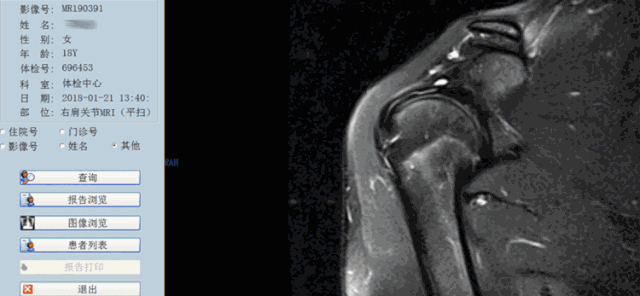

1期:肩袖尤其是冈上肌的水肿和出血,在年龄小于25岁的有症状患者中最为典型;

2期:炎性过程向纤维化过程(纤维变性和肌腱炎)转化,25-40岁患者多见;

3期:肩袖(部分或完全)撕裂,主要是40岁以上患者。

Neer分期提示我们,年龄是肩袖损伤诊断的重要因素,MRI诊断时也要注意这点,而且1、2期代表退变,应该选择保守治疗,3期为撕裂,也就是真正的肩袖损伤,大部分需要手术治疗。